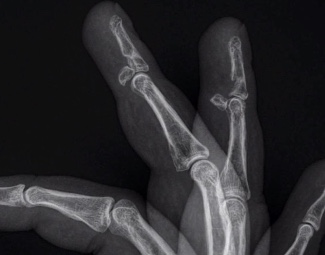

Fracture palmaire d’avulsion de l’IPP

- Assez fréquent en mécanisme d’hyper-extension

Fractures diaphysaire des métacarpes

- Boxeurs, Bagarreurs

- Patients Psy qui frappent contre un mur